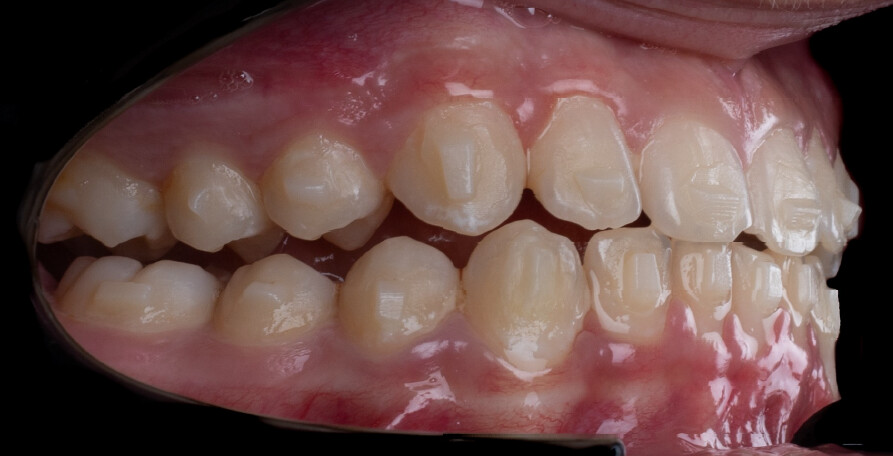

A 13-year-old male patient presented with a deep bite, characterized by near-complete coverage of the mandibular incisors. Clinical evaluation revealed bi-arch crowding, dental rotations, and proclination of the maxillary lateral incisors, contributing to the patient’s esthetic concerns. The facial profile was retrusive, consistent with mandibular retrognathism, and no significant periodontal abnormalities were detected.

The patient presented with a skeletal Class II relationship with bilateral molar and canine Class II and a Class II division 2 dental pattern. The deep bite was associated with anteroinferior crowding and an accentuated Curve of Spee. Facial analysis revealed good symmetry, a slightly increased lower facial third, and a convex profile characterized by mandibular and chin retrusion. Lip competence was mildly reduced, with a decreased nasolabial angle and mentalis hyperactivity, all of which compromised overall facial harmony.